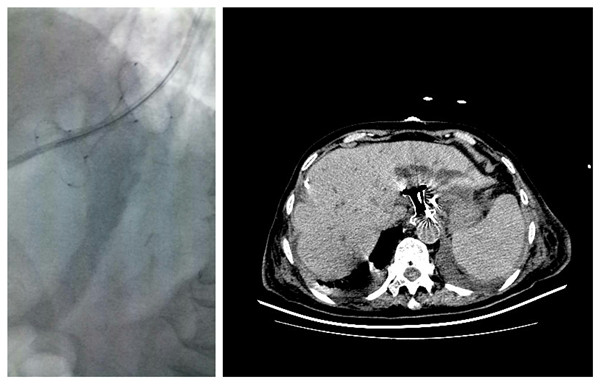

消化内科完成一例经胃壁胰腺假囊肿金属支架引流术,患者系高龄胆总管结石合并胰腺炎患者,并且胰腺炎反复发作并发巨大假性囊肿,腹腔脏器受压迫,引起肠道梗阻以及肾脏血管受压迫,多学科会诊后认为在行进一步治疗前,必须首先解决胰腺假性囊肿压迫问题。经多方协调,在放射科介入手术室的大力配合下,消化内科王进海主任与戴社教教授的指导,由消化内科马师洋主治医师与宋亚华主管护师进行手术操作,在超声内镜与DSA的引导下顺利完成假囊肿穿刺、扩张以及金属对吻支架释放,术后患者腹腔压力明显恢复正常,为后续治疗创造了良好的条件,这是我院首例采用这种特殊支架进行胰腺假囊肿治疗,在国内处于领先水平。

术中

术后